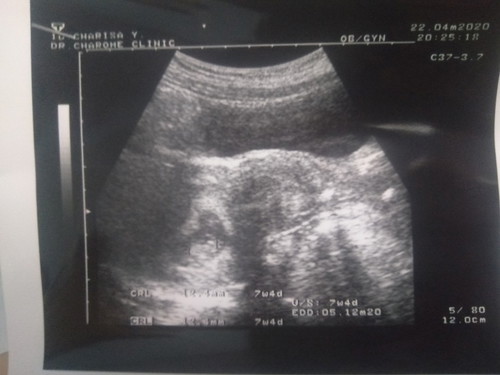

วันที่ไปซาวด์เราอายุครรภ์ได้9สัปดาห์ แต่ในเครื่องซาวด์ระบุขนาดเด็กได้1เซนนิดๆระบุ ประมาณอายุครรภ์ได้7สัปดาห์4วัน อยากรู้ว่าเวลาคลอดมีใครคลอดตรงกับอันไหนค่ะ ประจำเดือนครั้งสุดท้ายวันที่ 16 กุมภาพันธ์

ทั้งอัลตราซาวด์และการนับจากประจำเดือนครั้งสุดท้ายมีโอกาสคลาดเคลื่อนได้ค่ะ แต่จากผลอัลตราซาวด์จะแม่นยำกว่า คุณแม่ต้องรอลุ้นอีกทีค่ะ😊